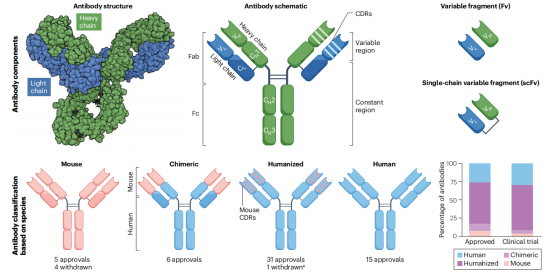

传统上,单克隆抗体是利用CesarMilstein和GeorgesKohler在1975年开发的杂交瘤技术生产的,该杂交瘤技术产生一系列小鼠单克隆抗体,稳定且经济有效,但是小鼠抗体注入人体会产生人抗小鼠抗体(HAMA)免疫效应,这限制了他们的功效,并增加了不良反应。随后嵌合抗体的出现也无法解决这以问题。为了进一步减少不必要的免疫反应,通过20世纪80年代开发的一种称为“人源化”的方法,增加了小鼠单克隆抗体的人源含量。人源化涉及仅将小鼠抗体的互补性决定区域(CDR)移植到人抗体的框架区域。除了小鼠杂交瘤技术以外,兔杂交瘤技术也被开发出来,用于生产针对肿瘤抗原的兔单克隆抗体。CDR嫁接方法已被用于人源化兔单克隆抗体,如针对间皮素的YP218,用于临床开发。在20世纪90年代发展起来的人源抗体噬菌体展示技术和表达转基因小鼠模型的人类抗体的两大技术的帮助下,全人源抗体得以产生。另外最新的单B细胞抗体开发技术进一步优化了抗体多样性和高通量的可及性。

目前进入临床实验的抗体要么是人源化的,要么是完全人源化抗体,根据之前的实验结果,人源化抗体和全人源化抗体在患者身上一般出现相似的效果。